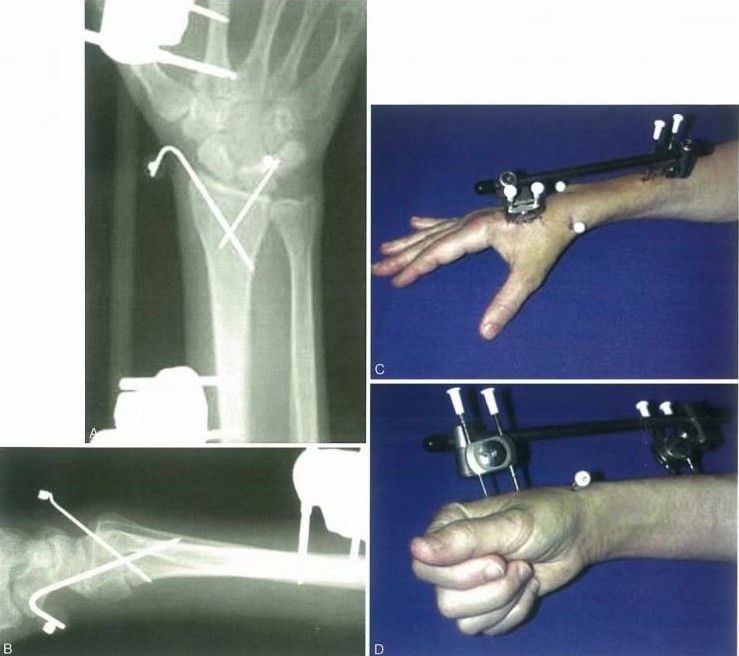

Opornice za zunanjo fiksacijo so uporabne za začetno ali dodatno zdravljenje pri specifičnih zlomih distalnega radiusa.

Zunanji fiksator nevtralizira aksialne napetosti, ki delujejo na distalni radius med kontrakcijo mišičnih skupin podlakti. Pritrditev je lahko čez zapestje ali pa ne ali pa je dodana dodatna fiksacija.

Vzporedni vlek ne obnovi popolnoma naklona dlani, vendar je nevtralni položaj sprejemljiv. Pooperativno je zapestje upeto v cevast mavec v rotiranem posteriornem položaju 10 dni, dokler bolečina in edem ne popustita.